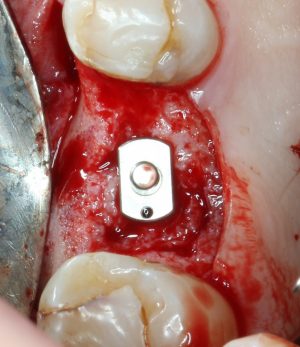

Кортикальная фреза погружается строго до отметки (см выше). В нашем клиническом случае (с синуслифтингом) это особенно важно, чтобы имплантат не улетел в субантральное пространство. Таким образом получаем лунку, полностью конгруэнтную будущему имплантату. Это очень-очень важно:

Пришло время вернуться к синуслифтингу и заполнить сформированное ранее субантральное пространство графтом (Geistlich Bio-Oss Pen):

запечатываем заполненное субантральное пространство:

Если лунка подготовлена правильно, то имплантат проваливается в неё почти полностью:

и докручивается до правильного положения несколькими оборотами.